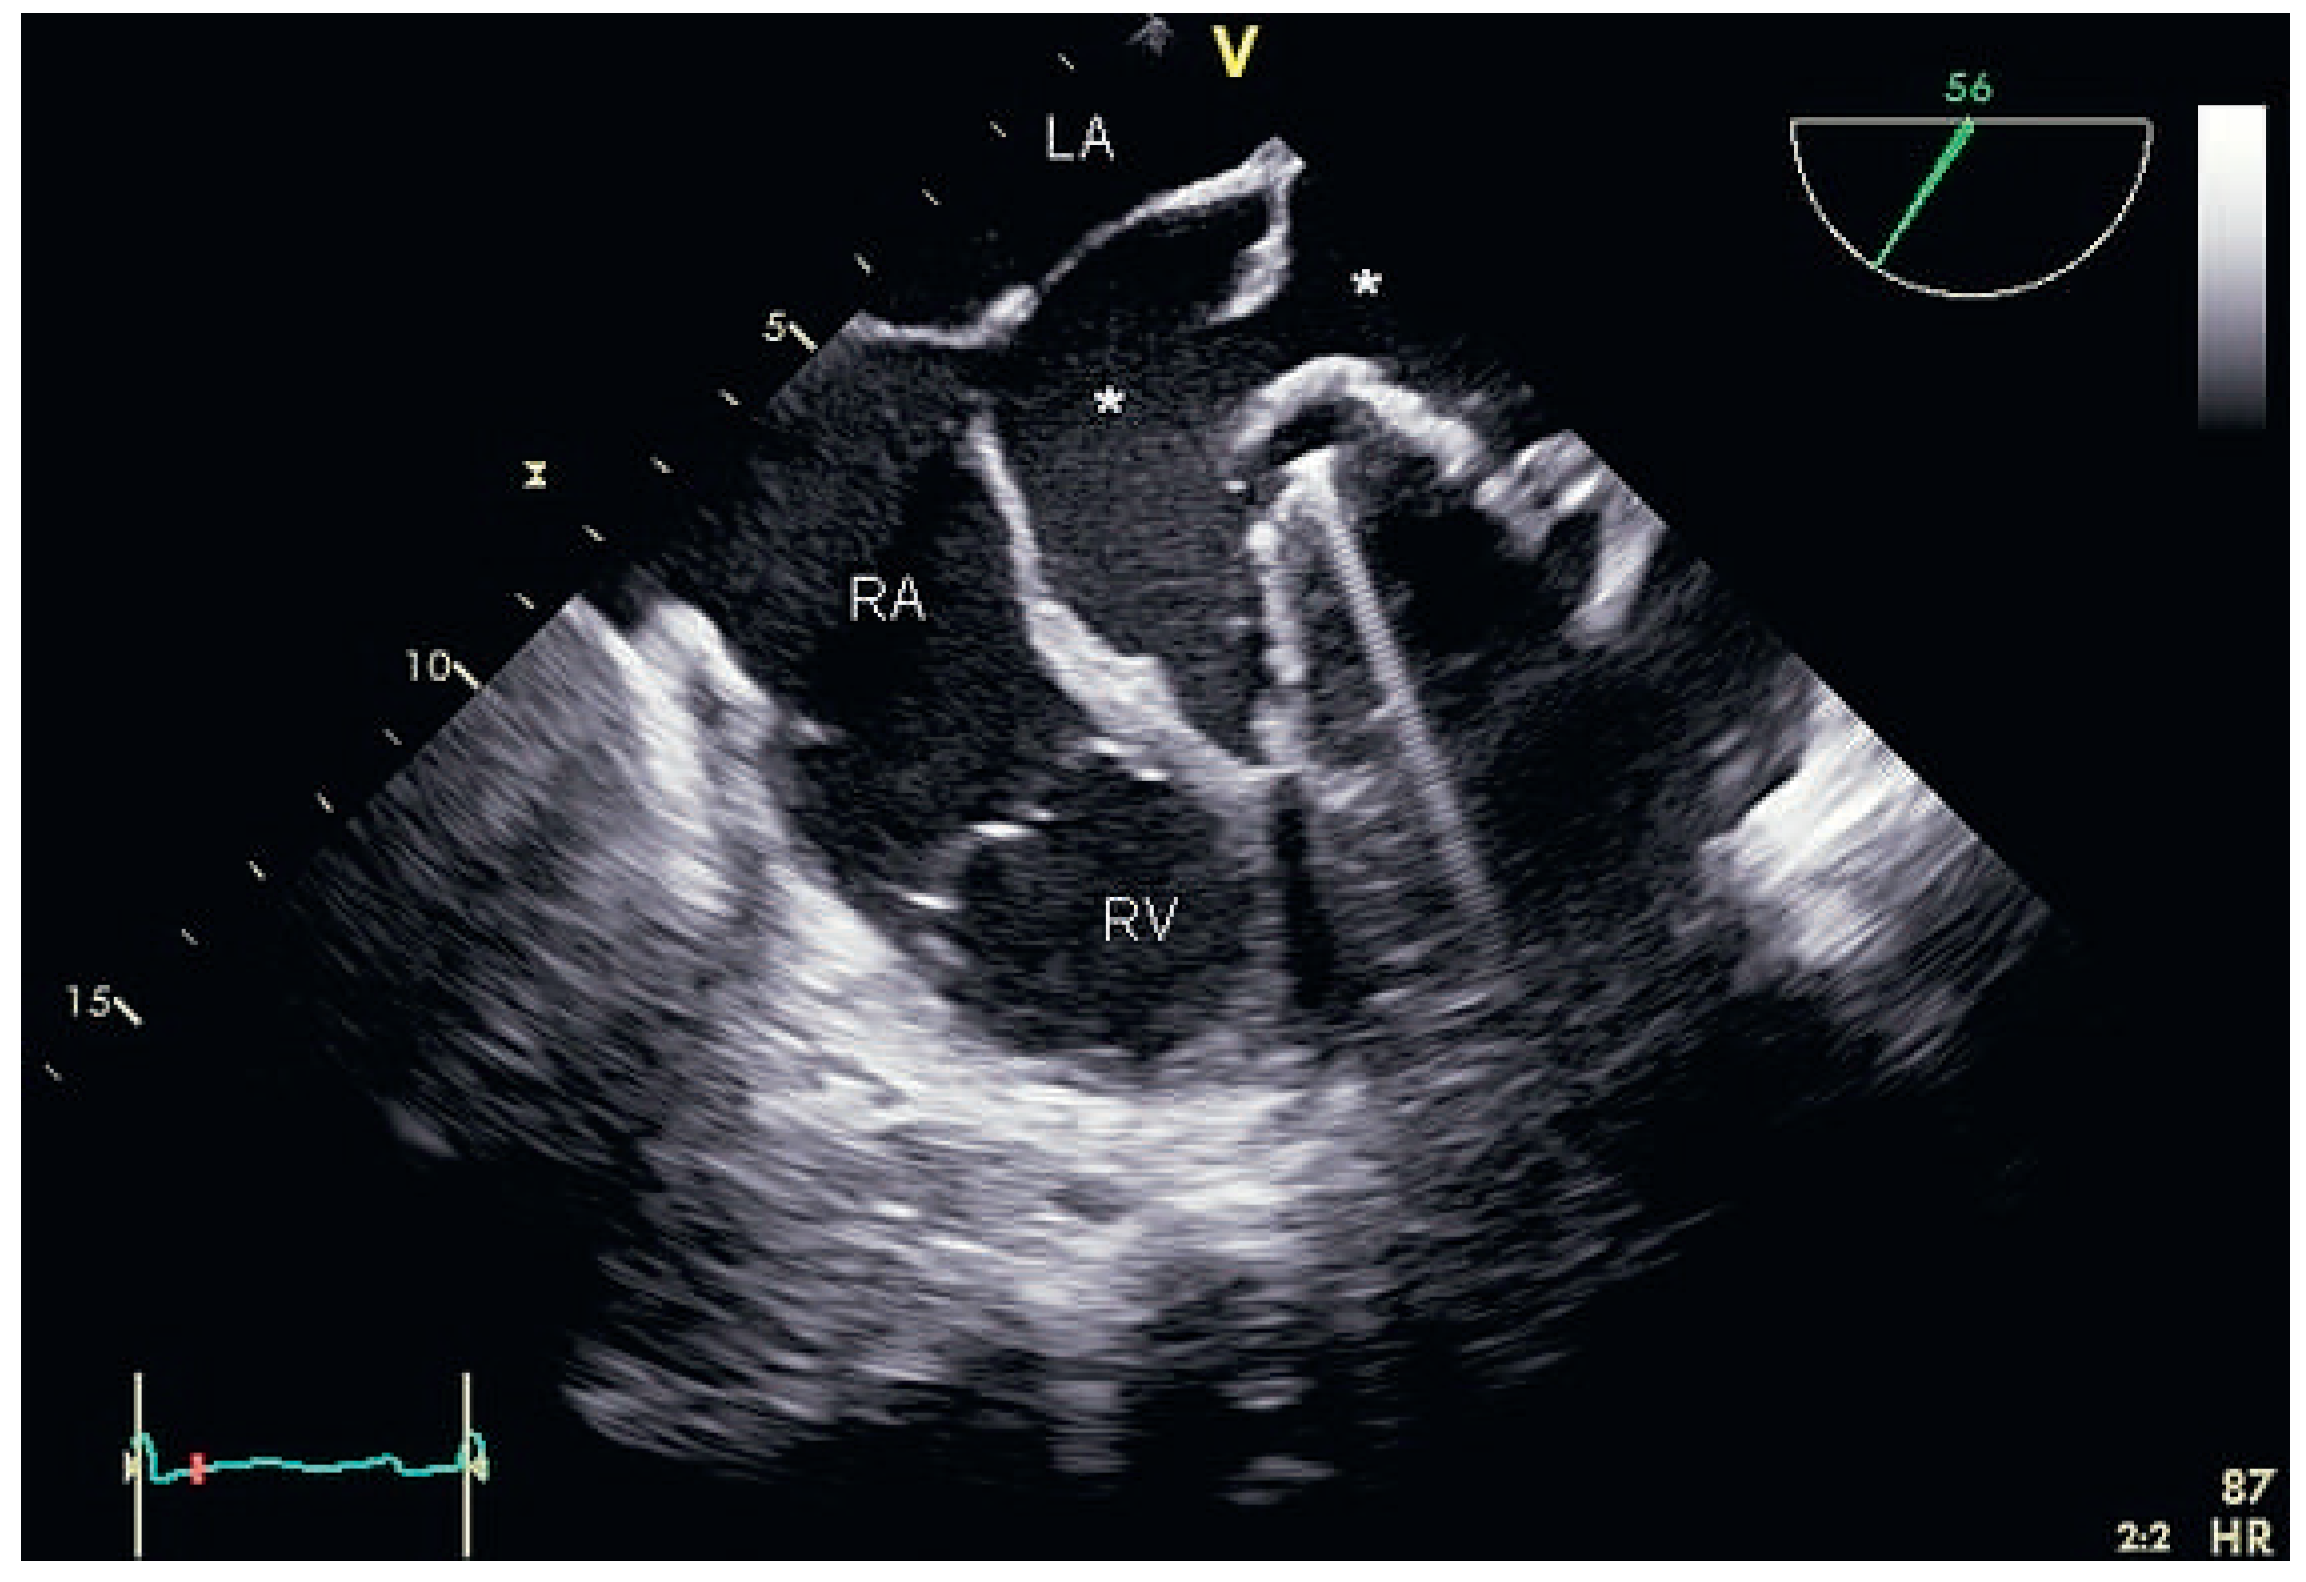

Partial Aortic Graft Disconnection Due to Endocarditis: A Rare Cause of Dynamic Coronary Artery Compression